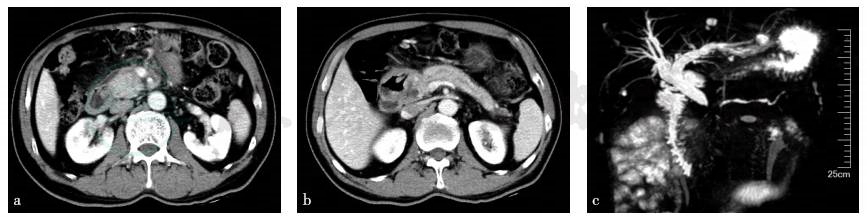

入院前特殊检查:CT检查和MRCP检查见图1。

图1 上腹部CT检查和MRCP检查(2017年6月)

a、b. 上腹部 CT;c. MRCP